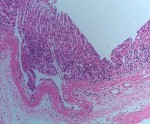

Lô mẫu cao toàn phần liều 150 mg/kg Trên các mảnh cắt thấy niêm mạc dạ dày bao gồm vùng biểu mô không tuyến và biểu mô tuyến. Vùng biểu mô không tuyến có cấu trúc và hình thái trong giới hạn bình thường. Vùng biểu mô tuyến thấy các tuyến trong mô đệm rõ cấu trúc, có hình thái và cấu trúc trong giới hạn bình thường. Mô đệm tăng nhẹ bạch cầu đa nhân trung tính. Mô dạ dày trong giới hạn bình thường, tăng nhẹ bạch cầu đa nhân trung tính. | |||||